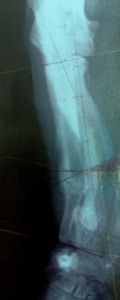

症例:柴犬 3歳

左後肢の完全挙上を主訴に来院されました。触診にて近位足根関節の過伸展を、レントゲン検査にて左足根関節周囲の軟部組織の腫脹、ストレス撮影によって距骨・踵骨と第4足根骨・中心足根骨間の脱臼および過伸展を認めました。

術中において、浅趾屈筋腱を剥離、内方へ牽引し、直接踵骨から第4足根骨までピンを挿入し(あらかじめ細いピンで下穴をあけておくとよい)、テンションバンドワイヤー法を併用し、関節軟骨の掻爬と海綿骨移植を実施しました。

術後レントゲン画像上に癒合が認められるまで約2ヵ月間は、運動を制限する必要があります。

術前正面像左関節の腫れ

左足根関節の軟部組織が腫脹しています。

術前正面像

術前側面像屈曲位

術前側面像伸展位